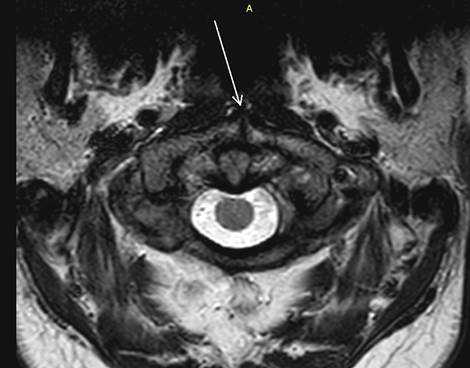

Результаты исследования и их обсуждение. Из 2857 мр-исследований шейного отдела позвоночника незаращение передней дужки атланта (рис. 4) было выявлено в 6 случаях (0,21±0,09%). Средний возраст обследуемых составил 43±5,4 года, возрастной диапазон выявленных случаев расщепления атланта составил от 34 до 48 лет. Из них мужчин было 1 (16,7%), женщин - 10 (83,3%). Диастаз расщелины варьировал от 0,3 до 2,1 мм, М = 1,4±0,7 мм.

Рис. 4. Аксиальный срез (Т2ВИ, стрелкой указан split atlas)